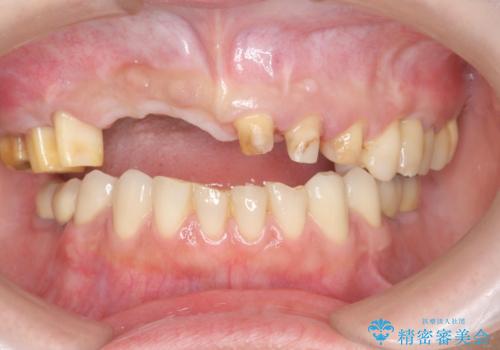

咬合性外傷による歯槽骨吸収 ブリッジ補綴

- 歯が揺れしっかりとものが噛めないことの改善を求めて来院されました。

保存の難しい歯の抜歯、保存できる歯の歯周病治療、欠損部位の歯槽堤形態回復を含めブリッジによる安定した咬合機能回復を計画します。